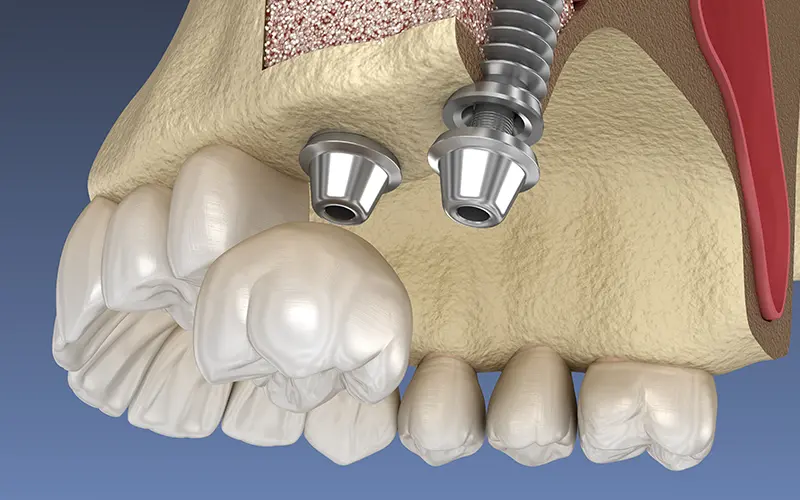

インプラント治療とは、虫歯や歯周病の進行などにより歯を失った場合、歯が抜けた場所の歯槽骨にインプラントと呼ばれるチタン製の人工歯根(インプラント体)を埋め込み、その上に人工の歯や義歯を装着することで、失った歯の機能を補う治療法です。

インプラント治療は、なくなった歯が一本の場合から、全てなくなった場合まで幅広い症例において有効です。インプラントと顎の骨が直接結合しているため、天然の歯とほとんど変わらない感覚で物を噛んだり、会話を楽しむ事ができ、見た目にも綺麗です。入れ歯やブリッジなどの治療法と違い、残っている歯を削ったり余計な負担をかけないため、ご自身の歯を長く持たせる事ができます。

アバットメントという支台をインプラントに装着し、STEP5で採取した歯型から作製した人工の歯をさらに装着します。